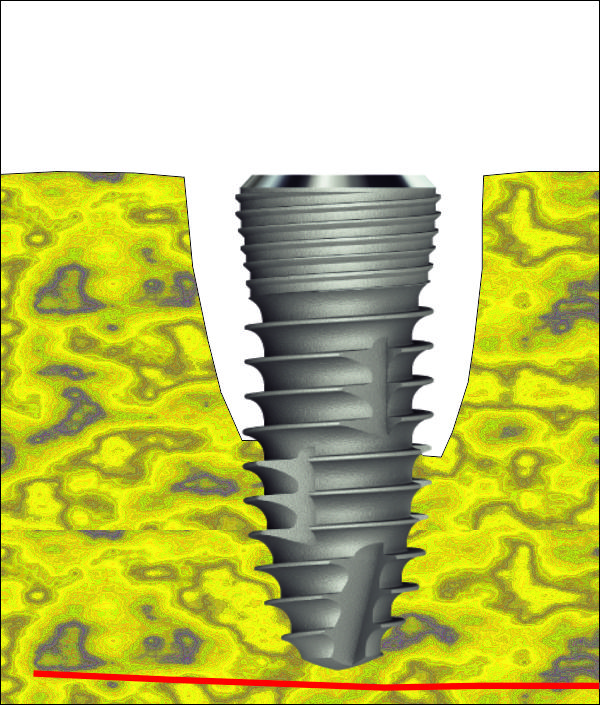

Първоначално разпробиване за имедиатно поставяне на зъбен имплант след

екстракция на долен молар. При горните моларни зъби ситуацията е идентична, но

има три корена вместо два. Идеята е да се центрова пилотната фреза в центъра на

интеррадикуларната септа, при което да се получи оптимално позициониране на

импланта. В много случаи фрезата се приплъзва встрани и започва да пробива във

възможно най-неудачното направление, така че е добре тя да се държи стабилно от

оператора, особено в началото. Добрите пилотни фрези имат силно заострен връх,

който е възможно да бъде поставен в една точка и да не се приплъзва встрани -

дори и при остра септа. При наличие на пародонтален проблем горната част на

преградата е резорбирана и фиксацията на фрезата е технически много по-лесна.

При употребата на

хирургичен водач определянето на правилната посока на разпробиване също е

доста по-лесно.